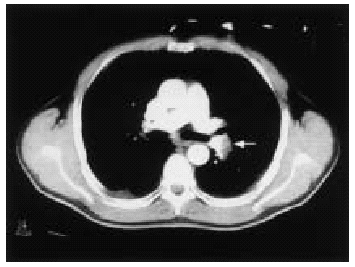

Debido a un nuevo episodio similar a los previos, acudió al servicio de urgencias de nuestro hospital. La exploración sistémica fue normal; en la radiografía de tórax se observaban 2 pequeños infiltrados en ambos lóbulos superiores, y en la gasometría la PaO2 fue de 56 mmHg; la PaCO2 de 27 mmHg y el pH de 7,49. En el electrocardiograma (ECG) se apreciaba una onda T negativa de V1 a V4. El hemograma, la bioquímica y el estudio de coagulación fueron normales. Se realizó una gammagrafía de ventilación-perfusión en la que se objetivó un déficit completo de perfusión del pulmón izquierdo (fig. 1). La tomografía computarizada (TC) helicoidal reveló una imagen compatible con un trombo en la arteria pulmonar izquierda y dos infiltrados triangulares de base periférica en LSD y LMD (fig. 2). En el ECO-Doppler de las extremidades inferiores no se objetivaron trombos en ninguna zona, con dilatación de las cavidades derechas y presión sistólica en la arteria pulmonar de 39 mmHg.

Figura 2. TC torácica. Imagen compatible con un trombo en la arteria pulmonar izquierda.

Permaneció estable hemodinámicamente (presión arterial de 110/60 mmHg; frecuencia cardíaca de 70-80 lat/min en RS) y con una SatO2 en torno al 95-97% con oxígeno por mascarilla al 40%. Con el diagnóstico de TEP masiva se realizó fibrinolisis con r-TPA (100 mg en 2 h). No hubo complicaciones y la rápida mejoría clínica (desapareció la disnea, frecuencia cardíaca de 40 lat/min; SatO2 del 100% con oxígeno a 2 l/min por gafas nasales) se comprobó con la realización de nueva gammagrafía y TC, en los que se constató la disolución del trombo y la reperfusión del pulmón izquierdo. Se continuó tratamiento con heparina sódica y posteriormente dicumarínicos orales (tasa de protrombina 30%; INR = 2,1). Tras 2 semanas de tratamiento fue dado de alta a su domicilio. Durante el ingreso se realizaron los siguientes estudios: estudio de hipercoagulabilidad, que fue normal; se descartó neoplasia subyacente (TC de tórax, abdomen y pelvis; ecografía abdomen y pelvis; gammagrafía ósea; marcadores tumorales); se descartó foco embolígeno (ECO-Doppler de miembros inferiores, flebogammagrafía; iliocavografía) y se descartó enfermedad reumatológica.